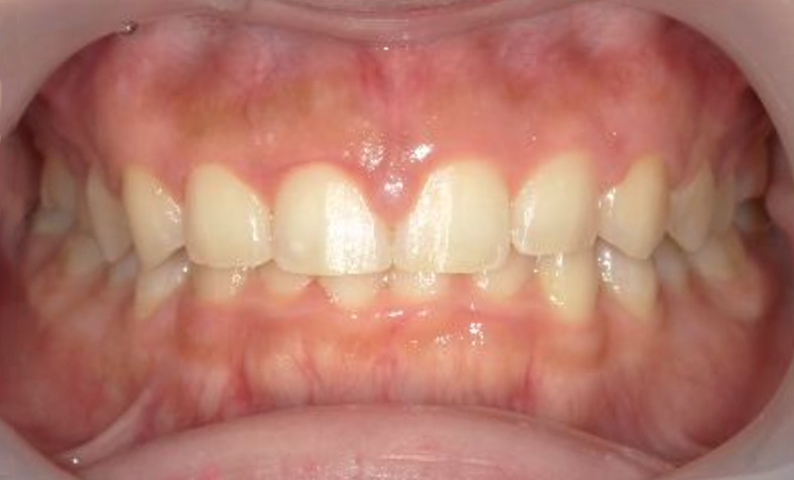

| 治療前 | 治療後 |

|---|---|

|